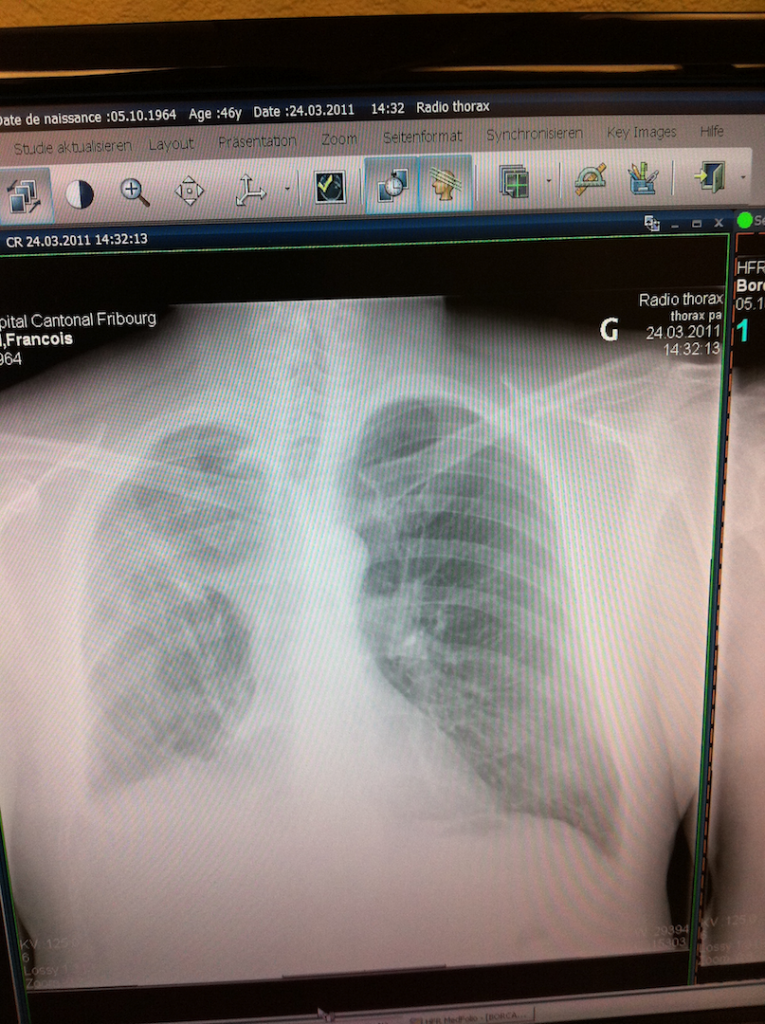

Je rencontre le chirurgien pour un premier contrôle le 24 mars. La radio suivante montre mon poumon après les opérations : le lobe restant s’est repositionné afin d’occuper l’espace, le corps humain déteste, paraît-il, les espaces vides !